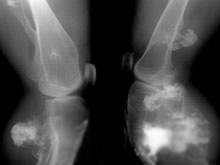

遺傳性多發性骨軟骨瘤的X線檢查示長骨幹上的骨軟骨瘤的特點是骨表面有骨性突起,與乾骺相連,由骨皮質及骨松質所組成,成對稱性、多發性。腫瘤基底部形狀各異,可分成有蒂(有一窄莖,頂部較寬)和無蒂(基底寬而扁)兩種。骨軟骨瘤常發生在乾骺端肌腱韌帶附著處,生長趨向與肌腱及韌帶所產生力的方向一致。若軟骨帽薄,邊界清楚,帶有規則點狀鈣化,這種表現為良性生長;若軟骨帽大且厚,邊界不清楚,帶有不規則的鈣化,應注意其惡性變的可能。骨軟骨瘤在手足短骨與長管狀的X線表現類似,在指、趾末節可有小的骨軟骨瘤存在,稱為甲下骨疣。

根據病史、臨床表現及X線檢查,診斷不難。經驗證明:如果在膝關節周圍骨上沒有外生骨疣,則遺傳性多發性骨軟骨瘤的診斷不能成立。